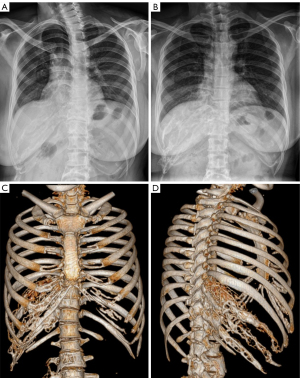

A previously healthy 50-year-old woman presented to the bone metabolism clinic of endocrinology at our medical center with moderate lower back pain and occasional numb pain in the right ribs. These symptoms had lasted for approximately 7 years without obvious limitation to her body flexion or movements. As a mother of two healthy teenage girls, she had no special medical, family, or psycho-social history of diseases. Not long ago, she had just visited a primary clinic, where radiographs showed massive osteolysis at multiple lumbar vertebrae and the right ribs (Figure 2A-2J). By physical examination to her body, mild percussion pain was detected at the T10-L3 level, but not in the right rib cage. Her body temperature, heart rate, and blood pressure were normal, and no coffee spots were observed. The thyroid gland was not enlarged, the thorax was not deformed or painful, the lungs were normal, the abdomen was normal on palpation, and no lower extremities were swollen. No deformity or pressure pain was observed in the spine or extremities. This patient was suspected of having GSD and was prescribed blood tests, urine tests, further radiographs, emission computed tomography (ECT), ultrasonography, and tuberculosis screening. The results of routine blood tests, blood sedimentation, blood lipids, liver function, kidney function, parathyroid function, thyroid function, vitamin D, blood tumor markers, calcium, phosphorus, magnesium, urine routine, 24 h urine calcium, 24 h urine phosphorus, blood immunoelectrophoresis, and urine immunoelectrophoresis were all normal. Abdominal ultrasonography results were also normal, as was bone density in the uninvolved area (Figure 2K-2N). ECT of whole-body bone imaging showed abnormally high uptake in the T10 and T11 vertebrae, right 8th–11th posterior ribs, lumbosacral vertebrae below L2, and bilateral sacroiliac joints (Figure 2O,2P). Additionally, ECT of the upper limb lymphography was normal. The patient was then referred to the orthopedic clinic for diagnostic bone biopsy to rule out bone related malignancies and to evaluate the indications for vertebral strengthening procedures such as percutaneous vertebroplasty (PVP). Upon admission to orthopedic ward, percutaneous puncture biopsies of T10 and T11 vertebrae were performed successfully under local anesthesia (Figure 3A-3E). The pathology results reported vertebral bone tissue and hyperplastic fibrous tissue without detectable malignancy to the bone (Figure 3F). The IHC staining was also performed and showed SMA (scattered +), desmin (−), CD34 (scattered +), S-100 (−), Ki-67 (bone marrow tissue index 80%), AE1/AE3 (−), CD15 (+), CD3 (+), CD20 (+), CD138 (+), and MPO (+). No PVP or other invasive procedures were recommended, considering the scattered yet symptomless osteolysis in the bones. This patient returned to the endocrinology clinic and was confirmed with GSD diagnosis. She was then prescribed a regimen of 5 mg of bisphosphonates per year, 0.25 µg of osteotriol every 2 days, 600 mg of calcium and 125 U of vitamin D per day, which was recommended until complete recession of disease. Allopathic treatment with Tylenol was also prescribed for occasional pain, and a regular follow-up plan was scheduled every 3 months. She returned to the outpatient clinic with relief of lower back pain, mild pleural effusion, and no onset of new symptoms or signs of newly onset of osteolysis after 3 months of treatment (Figure 4A). The patient was advised to visit the respiratory medicine clinic for monitoring of minor pleural effusion and was referred to the interventional center of radiology for undecided indications of pleural biopsy. Considering that there was no particularly safe puncture access according to the CT imaging, and that minor pleural effusion did not cause significant chest tightness, the radiologist recommended re-evaluation by imaging within 3 months. The patient continued with the original regimen and returned 3 months later with almost no back pain. Repeated imaging revealed reduced pleural effusion and static osteolysis on the 12th months revisit (Figure 4B) and 18th month revisit (Figure 4C,4D). During the entire diagnostic and therapeutic process, this patient fully cooperated with the diagnostic and therapeutic procedures. She gladly adhered to the regimens without adverse or unanticipated events. With the current treatment plan, the patient’s condition gradually stabilized, and remission was gradually achieved. Until the eighteenth months since the first visit, the patient had continued with her normal life. The medical expenses are affordable with basic citizen insurance, and her mind is relieved and healthy.